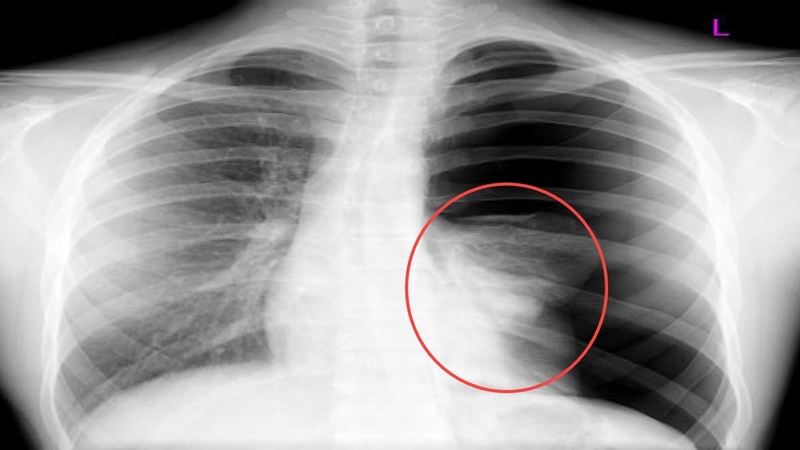

Viêm tụy cấp không trực tiếp gây tràn dịch màng phổi, vậy tại sao viêm tụy cấp gây tràn dịch màng phổi? Viêm tụy cấp có thể dẫn đến các biến chứng nguy hiểm khác, trong đó có một số biến chứng có thể gây ra tràn dịch màng phổi. Một trong những biến chứng của viêm tụy cấp là viêm phúc mạc, khi đó các tế bào của tụy chết do bị tổn thương. Khi xảy ra viêm phúc mạc, có thể có sự tích tụ mủ trong hoặc xung quanh tụy, gây ra áp lực và làm phù tụy. Áp lực này có thể lan sang các cơ quan lân cận, bao gồm cả phổi, gây ra tràn dịch màng phổi.

Tóm lại, viêm tụy cấp không gây trực tiếp ra tràn dịch màng phổi, nhưng có thể dẫn đến các biến chứng khác, bao gồm viêm phúc mạc và viêm phổi, cả hai đều có thể dẫn đến tràn dịch màng phổi.

Thông tin "tại sao viêm tụy cấp gây tràn dịch màng phổi?" hẳn đã giúp bạn nhận thấy sự nguy hiểm của căn bệnh này với sức khỏe là không hề nhỏ. Khi tụy bị viêm cấp, các tế bào sẽ bị tổn thương và dễ dàng bị xâm nhập bởi vi khuẩn hoặc vi trùng, dẫn đến nhiễm trùng tụy. Nếu không nhanh chóng điều trị kịp thời và đúng cách, nhiễm trùng này có thể lan sang các cơ quan khác trong cơ thể, đây chính là nguyên nhân gây ra các biến chứng nguy hiểm như tràn dịch màng phổi, suy tim, suy thận và đôi khi có thể dẫn đến tử vong. Do đó, việc phát hiện và điều trị viêm tụy cấp sớm rất quan trọng để ngăn ngừa những biến chứng nguy hiểm này xảy ra.